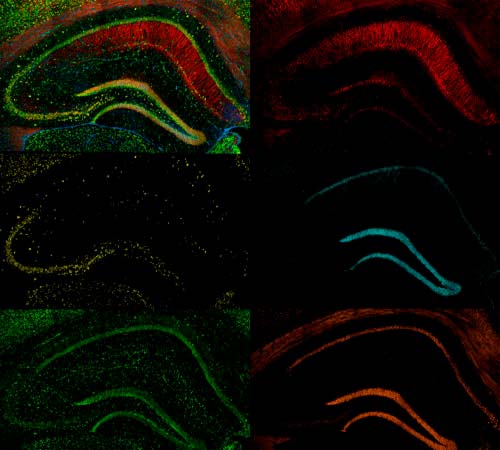

Resumen:El grupo de investigación BRABE, del inglés, BRAIN, cerebro y BEHAVIOUR, comportamiento, está adscrito a la Facultad de Ciencias de la Vida y de la Naturaleza (FCVN). Es un grupo constituido por 11 profesionales dentro del campo de la psicología, biología y de la actividad física y del deporte que trabaja conjuntamente para la consecución de una investigación excelente y de calidad en el campo de la Psicobiología. Su labor científica consiste en elucidar las funciones psicofisiológicas y los mecanismos patológicos asociados a los procesos neurodegenerativos y el envejecimiento. Nuestro grupo, con estos enfoques complementarios, está trabajando para cerrar la brecha de conocimiento existente, y para permitir la identificación de enfoques terapéuticos que se necesitan con urgencia para prevenir o aliviar la neurodegeneración y los procesos asociados al envejecimiento. Para realizar esta tarea, el grupo BRABE cuenta con personal investigador permanente de la Universidad Nebrija y personal externo afiliado de universidades nacionales e internacionales de primer nivel.

• Modelos animales de neurodegeneración, prematuridad y envejecimiento

• Estudio de las poblaciones gliales

• Identificación de biomarcadores moleculares y celulares de los procesos neurodegenerativos:

En esta línea exploraremos los potenciales biomarcadores, los cuales no solo son fundamentales para el diagnóstico y el pronóstico en los pacientes que padecen procesos neurodegenerativos, sino que también desempeñan un papel importante en el proceso de desarrollo de fármacos, para la validación de las dianas terapéuticas.

• Análisis de los procesos neuroinflamatorios:

La neuroinflamación es un factor importante de muchas enfermedades del sistema nervioso central (SNC) y se cree que aliviar la neuroinflamación reduce la gravedad de la enfermedad y mejora el resultado del paciente en la mayoría de los casos. En esta línea de investigación exploramos la patología neuroinflamatoria, distinguiendo entre inflamación aguda y crónica, examinando las contribuciones de los principales tipos celulares gliales.